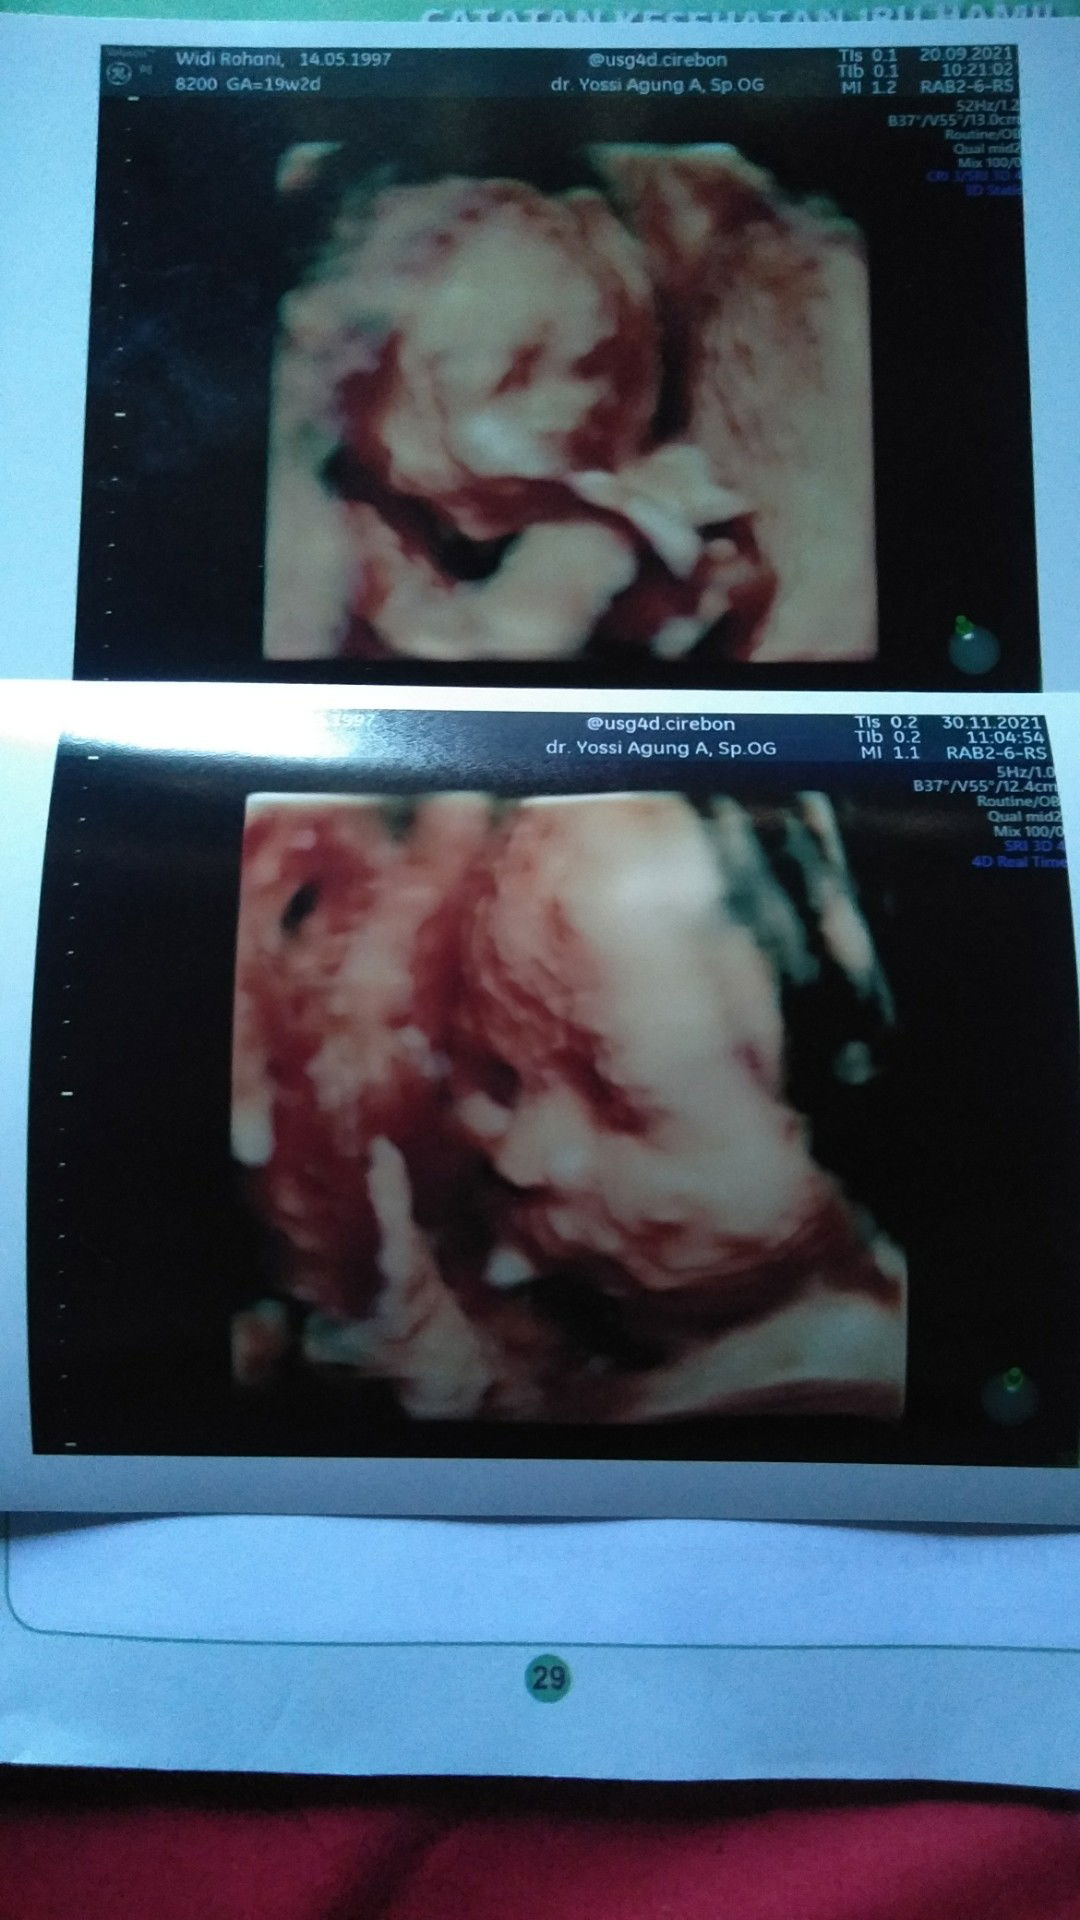

kehamilan ke 4 anak pertama 5 tahun anak kedua n ketiga keguguran dan ini lagi hamil anak ke 4.. semoga Beby ku sehat n aku juga kuat..

bissmillah..saya usia 26th..hamil anak pertama..masih usia kehamilan 6 mingguan..semoga menjadi rezeki untuk saya dan calon anak 😇

Bismilah ya Allah di kehamilan ini mudah²an dilancarkan segala prosesnya, dapet rezeki dari mana pun arahnya untuk si jabang bayi✨

Bismillah ,aku hamil anak pertama usia kandunganku 5minggu 5hari, semoga kali ini rezekiku dan calon anakku🥰😇, Berkah slalu😇